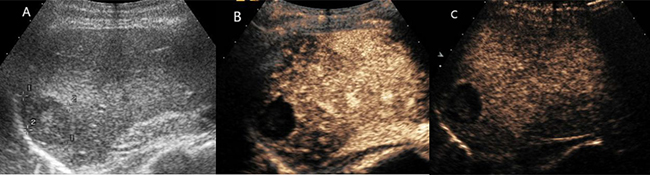

Figure 4: Hepatic hemangioma with no enhancement in all vascular phases. (A) Ultrasound revealed a hyperechoic mass with multiple spotty calcifications in hepatic segment VII. (B) and (C) CEUS showed none enhancement throughout the whole vascular period. (D) T2- weighted MR images revealed a high signal intensity lesion with fluid–fluid level. (E) Enhanced magnetic resonance showed no contrast enhanced in arterial phase.

Figure 5: Hepatic hemangioma with septa enhancement in all vascular phases. (A) Ultrasound revealed a mix-echoic mass comprised of a multilocular cystic part in the periphery and a stellate echogenic part in the centre. (B) and (C) CEUS showed isoenhanced with septa and stellate part, no enhancement with cystic part. (D) The lesion showed bright signal intensity on T2-weighted MR images. (E) On enhanced magnetic resonance, the septa part enhanced with contrast and the periphery cystic part was not enhanced.